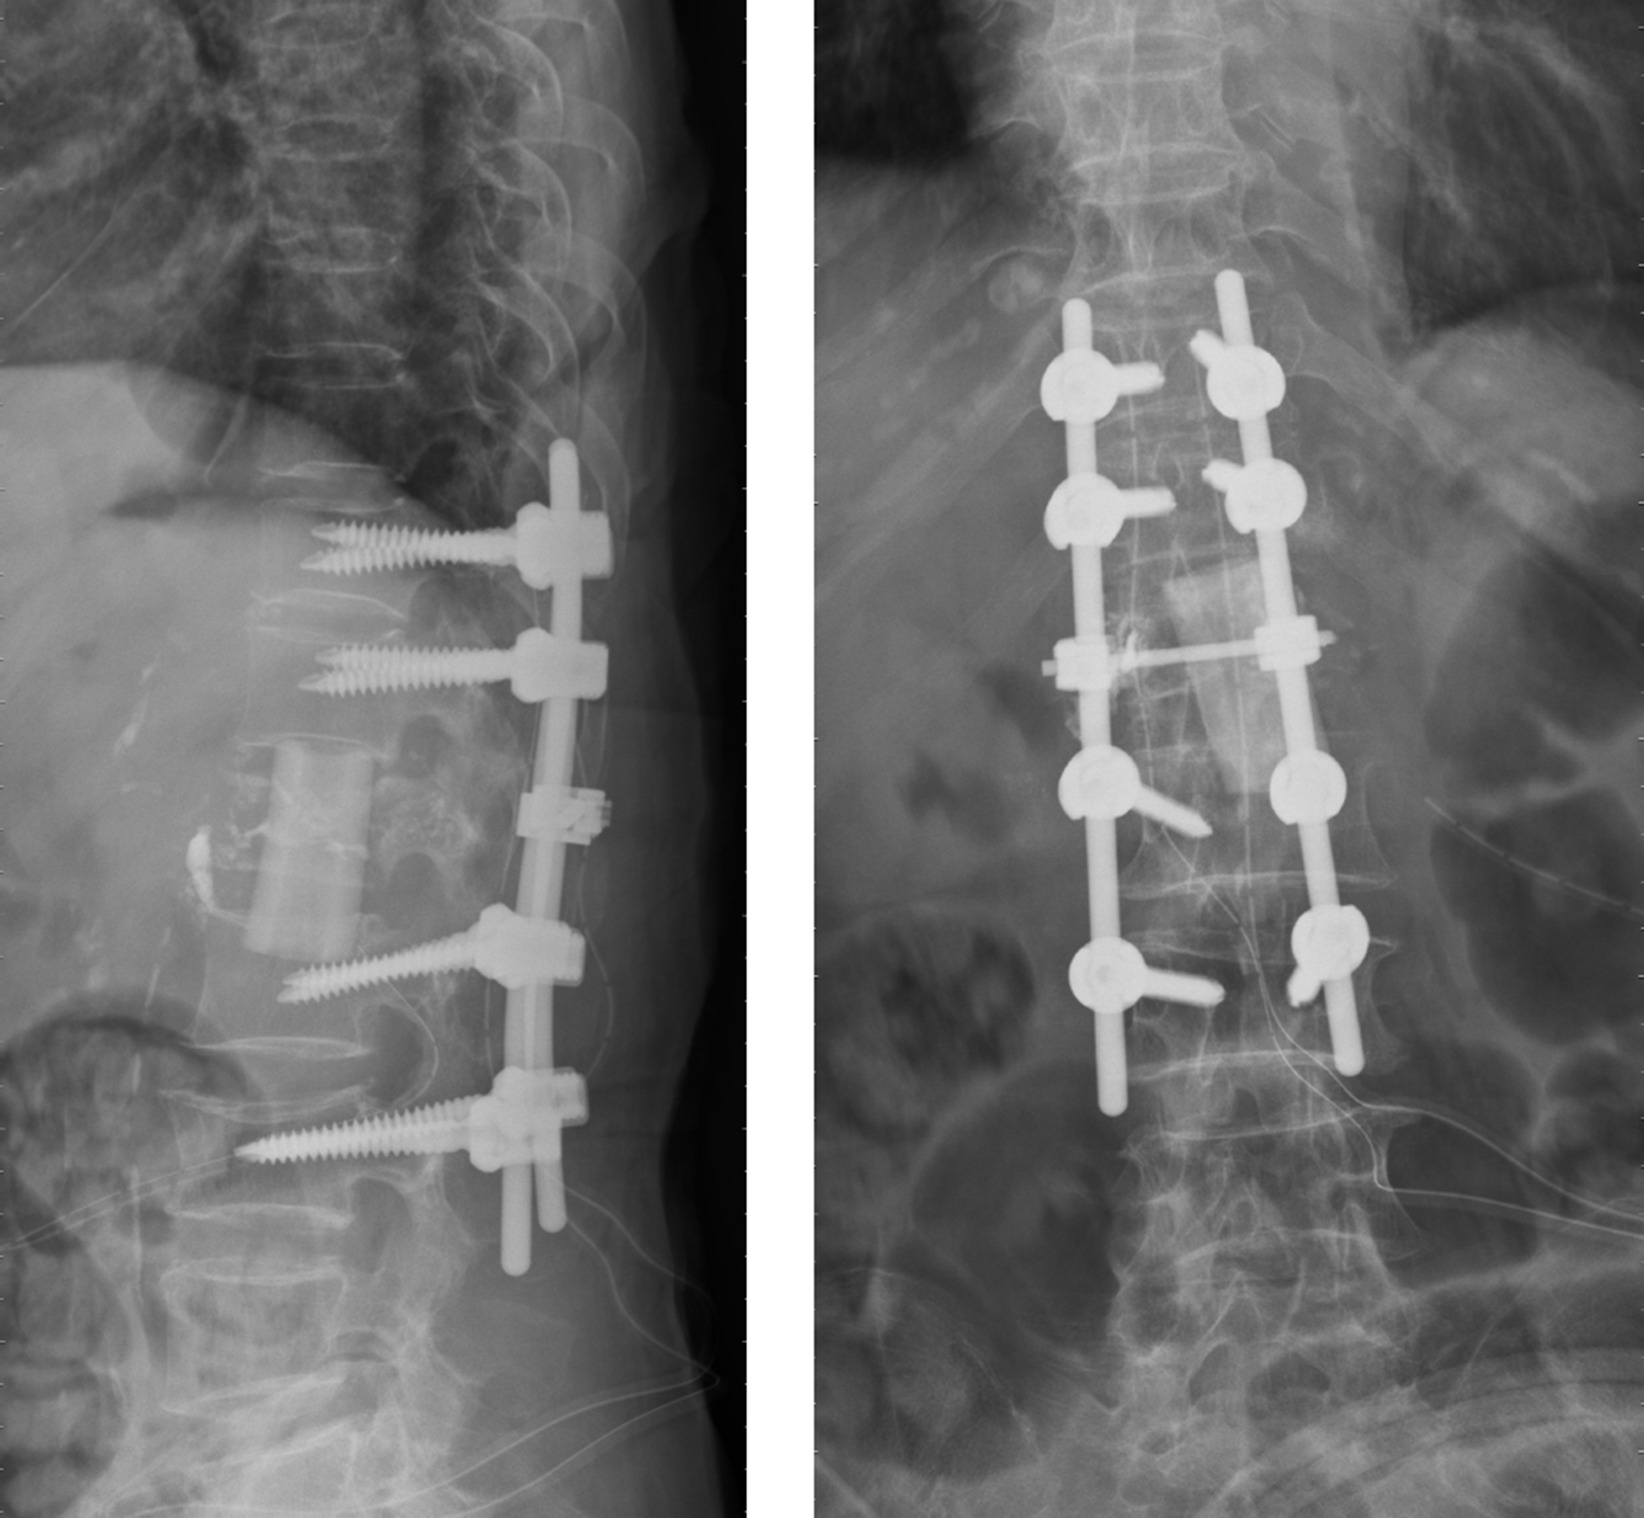

Lumbar Spine Surgery: An Overview

Lumbar spine surgery is often recommended for patients experiencing severe back pain or dysfunction due to conditions like degenerative disc disease, herniated discs, spinal stenosis, spondylolisthesis or degenerative lumbar scoliosis. This procedure aims to alleviate pain, restore function, and improve the patient’s quality of life.

Indications for Lumbar Spine Surgery

Before surgery, patients must undergo a thorough evaluation, including physical exams and imaging tests, such as X-rays or MRIs. The surgeon will explain the specific condition and the type of surgery that would be most beneficial. Common types of lumbar spine surgery include discectomy (removal of a herniated disc), laminectomy (removal of part of the vertebra to relieve pressure on the spinal cord), instrumentation (putting pedicle screw in vertebra) and spinal fusion (joining two or more vertebrae to stabilize the spine).

The lumbar spine surgery can be Minimally Invasive (Endoscopic, Tubular) or traditional open surgery chosen by the surgeon to address the patient condition/pathology.